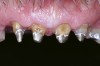

Many times, endodontically treated teeth are compromised in their overall remaining coronal structure because of caries, previous restorations, trauma, and the endodontic access. Reeh et al evaluated reduction in tooth stiffness as a result of endodontic and restorative procedures.19 They found that the tooth was inherently stiff and resistant to flexion. Once a tooth was prepared, the rigidity of the tooth was reduced. An occlusal cavity preparation reduced tooth stiffness by 20%, and loss of marginal ridge integrity with a mesial-occlusal-distal preparation reduced cuspal stiffness by 63%. In comparison, an endodontic access preparation reduced relative tooth stiffness by a mere 5%. Other studies have confirmed that the loss of tooth structure makes endodontically treated teeth more susceptible to fracture.20-22 Some practitioners believe that posts placed in the restoration of an endodontically treated tooth reinforce that tooth.7 Research studies have demonstrated that metal posts, both prefabricated and cast, may in fact lead to root fracture (Figure 1A and Figure 1B).23-25

Figure 1a  Mandibular first molar with distal root fracture. Note the root canal perforation and post in the mesial root.

Figure 1a

Figure 1b  Mandibular second premolar with a short, large-diameter post that has created a vertical root fracture.

Figure 1b